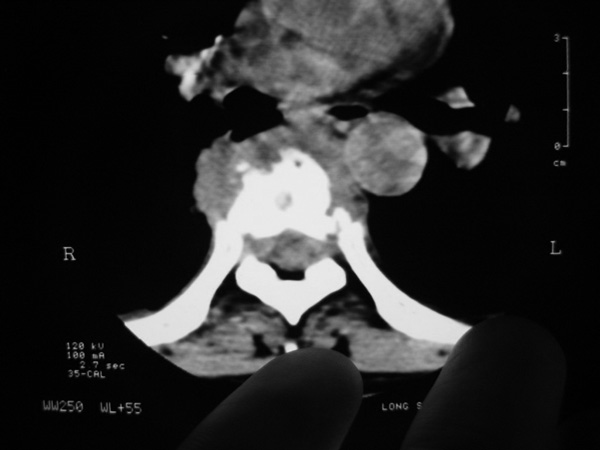

女,45岁,胸背部疼痛2个月。t6、7胸椎病变。

椎旁肿胀的软组织内可见气泡影,对脊柱的化脓性和结核性的鉴别有帮助吗?

支持胸椎结核伴冷脓肿伴双侧胸腔积液.为何无肺窗.

支持胸椎结核伴冷脓肿伴双侧胸腔积液

胸椎结核伴冷脓肿伴双侧胸腔积液

胸椎体骨质破坏伴死骨形成,椎周环状软组织肿胀,范围较长,考虑胸椎结核伴冷脓肿形成。鉴别;1转移性肿瘤;椎弓根骨质破坏多见,软组织肿块局限。椎间隙尚存。有原发肿瘤病史。2,淋巴瘤;骨质破坏 然骨皮质轮廓线尚存,当椎管骨示环状软组织影时有一定特异性。病变较局限。建议mri增强,观察冷脓肿与软组织肿块很有帮助。

支持胸椎结核伴冷脓肿形成,伴双胸腔积液,要是有肺窗就好,可行穿剌活检.